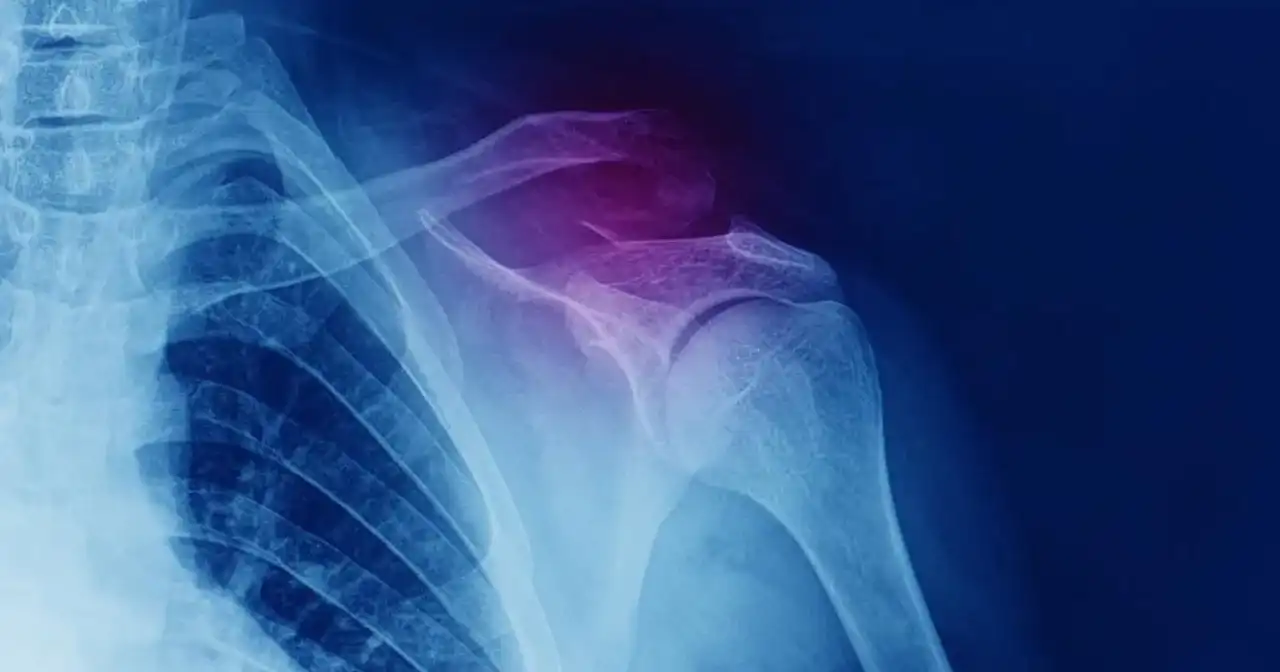

Złamany obojczyk: Ile trwa gojenie i powrót do zdrowia?

Złamany obojczyk: ile trwa zrost i powrót do sprawności (48 tyg., 36 mies.), czynniki wpływające i praktyczne porady rehabilitacyjne. Sprawdź przewodnik.